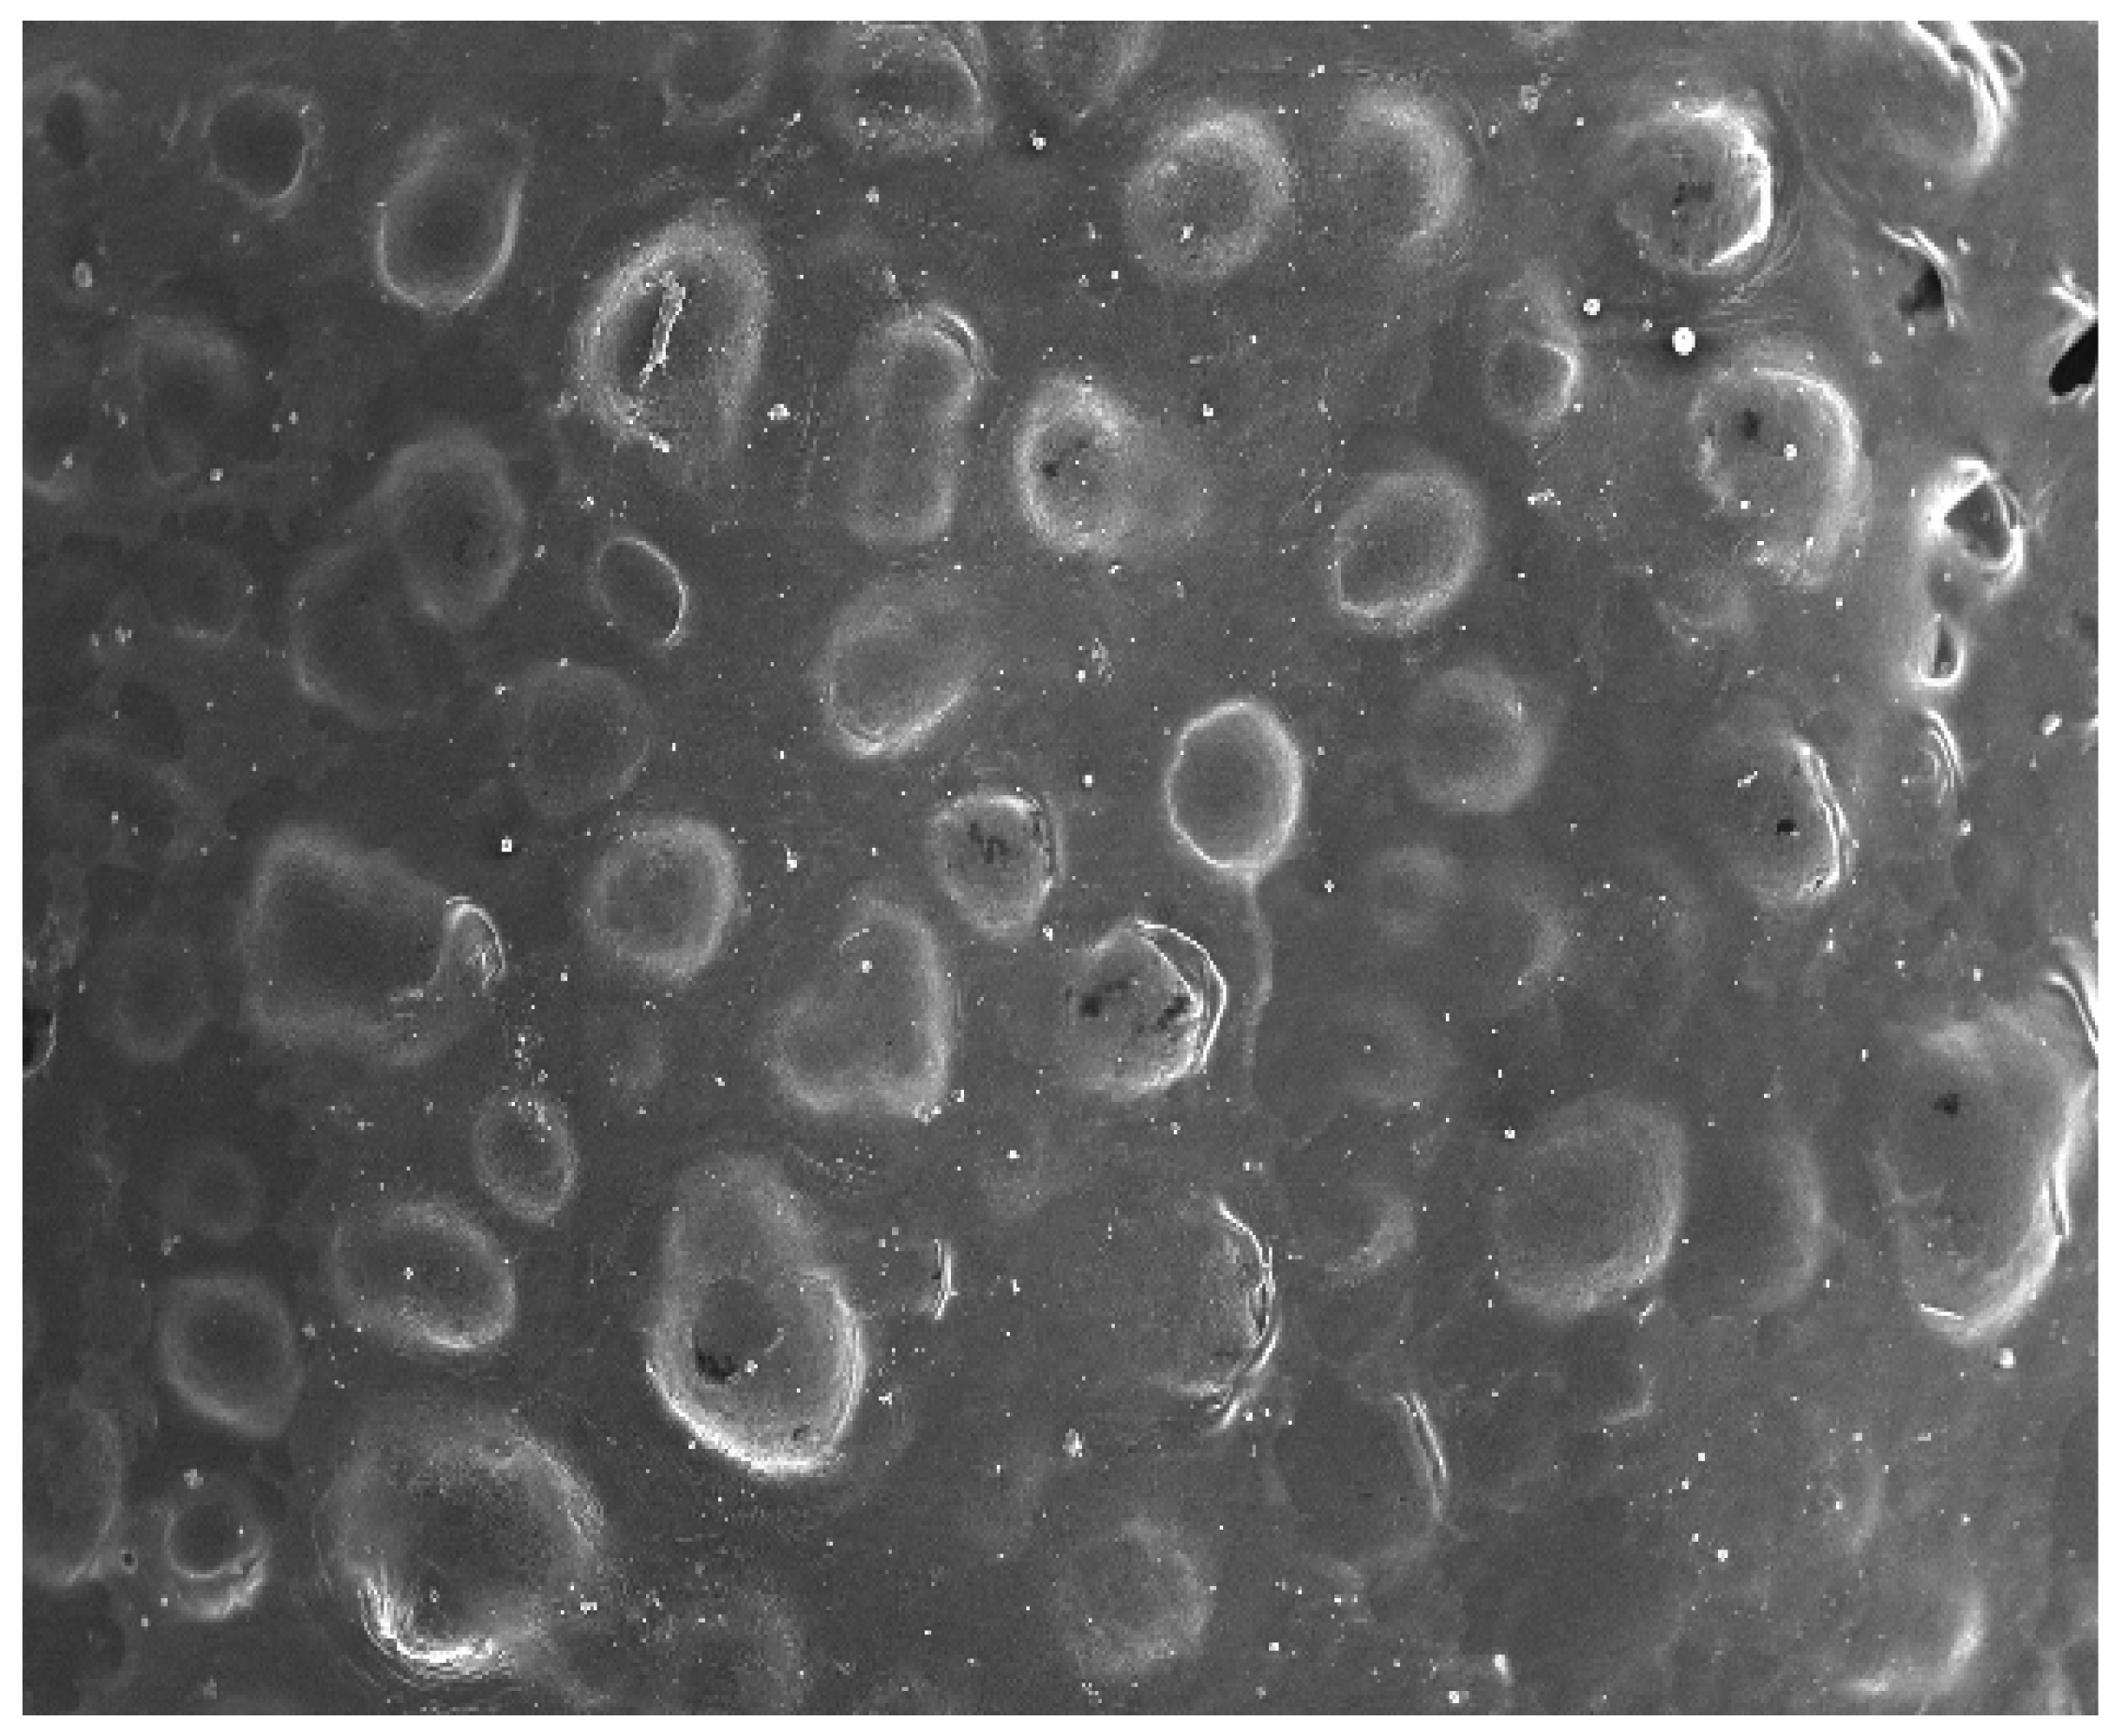

3.6. Vesicle Size, Zeta Potential and Surface Morphology